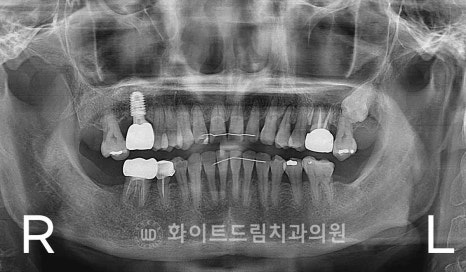

[동일 인물이며 동일 환경에서 촬영됨 / 강남역어금니임플란트 : 23.04.04 - 23.09.27]

약 8–10 mm 정도의 임플란트를 안정적으로 식립하려면

최소한 상악동을 5 mm 이상 거상해야 했기 때문에,

측방 접근법(Lateral window sinus lift)을 이용해 수술을 진행했습니다.

수술 시, 측방부에 작은 골창(window)을 형성한 뒤

상악동막을 조심스럽게 들어 올리고,

그 공간에 골이식재를 주입하여

부족했던 치조골 높이를 보강했습니다.